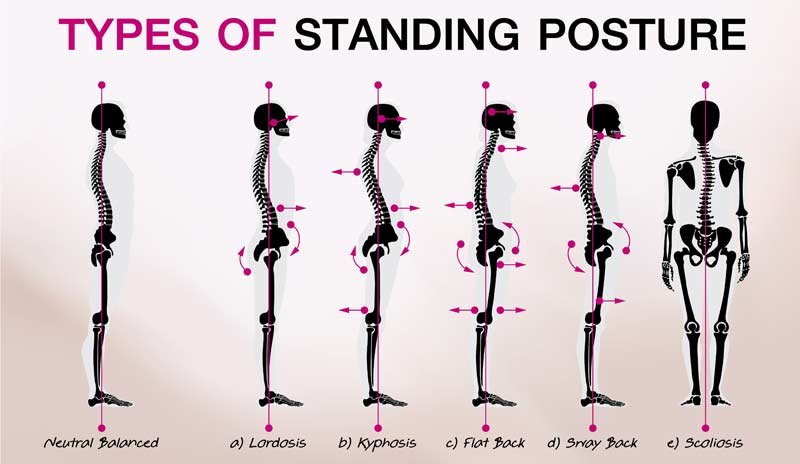

Improper Posture

Is posture important? How does it affect athletes? Should I be worried about it? In this article, Emma breaks it down.